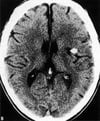

Инфаркт средней мозговой артерии

В области головного мозга, снабжаемого правой средней мозговой артерией, виден большой светлый очаг инфаркта.

By permission of the publisher. From Furie K, et al: Cerebrovascular disease. In Atlas of Clinical Neurology. Edited by RN Rosenberg. Philadelphia, Current Medicine, 2002.